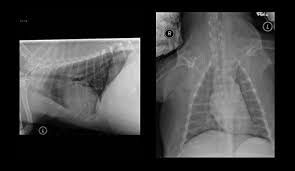

Pneumonia Dog Lung Cancer Xray : The Benefit Of Three View And Left Lateral Thoracic And Abdominal Radiographs Tips For Taking Radiographs In Your Veterinary Practice 2 Important Tips For Taking X Rays In Your Veterinary Practice Tips For Taking X Rays / Pneumonia in dogs can have different causes:. Lung cancer often misdiagnosed as pneumonia urges requests for second medical opinions. Signs of the primary tumors in dogs. Typical signs of bacterial pneumonia include fever, difficulty breathing, lethargy and coughing. The first of these possibilities could be investigated by bronchoscopy. The second kind of lung cancer in dogs is called metastatic lung cancer, which means the cancer originated somewhere else in the body, but has spread to the lung.

Aspiration Pneumonia In Dogs Central Toronto Veterinary Referral Clinic from ctvrc.ca A definitive diagnosis of lung cancer requires a sample of tissue (biopsy). Pneumonia is a lung infection that leads to breathing difficulties and fluid in the lungs. But in some rare cases, it may be a lung cancer (primary or secondary). My dog had pneumonia come on quickly this last august, we took her to the local er at 3am when we noticed her breathing labored and strange behavior. X rays are very helpful in the diagnosis of lung cancer in dogs. Typical signs of bacterial pneumonia include fever, difficulty breathing, lethargy and coughing. A retrospective study of 1011 hospitalized patients with pneumonia was undertaken to assess the value of routine convalescent chest radiography for detection of underlying lung cancer. The bronchioles end in the small sacs called.

A definitive diagnosis of lung cancer requires a sample of tissue (biopsy). X rays are very helpful in the diagnosis of lung cancer in dogs. Primary lung cancer are frequently located in the caudal (towards the hind end of the pet) lung lobes, however can be located in any lung lobe and are usually a single mass in the lungs, unless the tumor has spread. If your dog has a chronic cough, you'll need to rule these out. The first of these possibilities could be investigated by bronchoscopy. A definitive diagnosis of lung cancer requires a sample of tissue (biopsy). The second kind of lung cancer in dogs is called metastatic lung cancer, which means the cancer originated somewhere else in the body, but has spread to the lung. Bacterial pneumonia is an inflammation of the lung usually caused by bacterial or viral infection but can be caused by inhalation of an irritant. The respiratory system consists of the large and small airways and the lungs. Lung cancer is actually the number one killer when it comes to cancers. But in some rare cases, it may be a lung cancer (primary or secondary). In both cases, you may have. Typical signs of bacterial pneumonia include fever, difficulty breathing, lethargy and coughing.

However, some dogs only experience weight loss (despite a good appetite) and/or lack of energy. In both cases, you may have. Pneumonia in dogs can have different causes: Often, people with recurrent bouts of pneumonia tend to have unidentified lung cancer that can progress to advanced stages without appropriate treatment. Malignant tumors trigger inflammation in surrounding normal lung tissue, and they may obstruct.